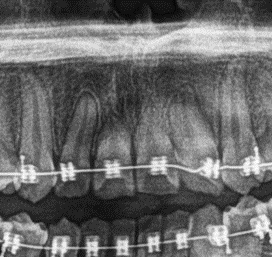

Fig.2

En la región anterosuperior (Fig.2) se observa un marcado acortamiento de la longitud radicular de los incisivos centrales superiores. Dicho signo radiográfico puede tratarse de una anomalia en el tamaño radicular versus la excesiva aplicación de fuerzas mediante el tratamiento de ortodoncia.